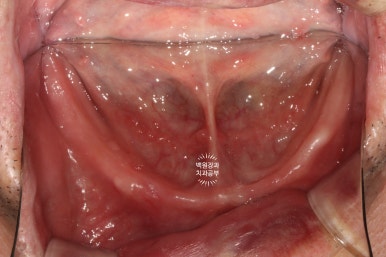

아래는 이가 하나도 없어 얼마 전 다른 치과에서 제작한 전체틀니를 사용하고 계셨고,

아래턱 전체틀니는 무지하게 잘 떨어집니다.

틀니접착제를 사용해도 마찬가지죠..

아래턱에는 혀가 있기 때문에, 전체틀니를 사용하면 말하거나 밥먹을 때 무조건 바로 떨어져버립니다....

그래서 입안 사진 찍는 것 조차 힘들었어요. 자꾸 떨어졌기 때문에......

이런 불편함을 안고 어떻게 식사를 하고 어떻게 건강을 유지하실 수 있겠어요...

그래도 완전틀니를 제거하고 본 아래턱의 뼈 상태는 나쁘지 않았습니다.

틀니를 오래 쓰신 분들을 보면, 틀니에 눌려 잇몸뼈가 상당히 많이 사라져버린 분들도 많은데요....

다행히 임플란트를 심을 정도의 뼈는 남아있으신 상태였습니다!!!!